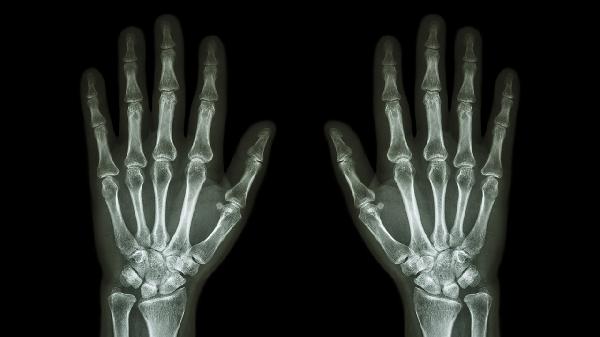

手指关节处突然乌青可能是由外伤、血液疾病或血管异常等原因引起的。乌青通常表现为皮下出血,可能伴有疼痛或肿胀,建议及时就医明确原因。

手指关节处受到撞击、挤压或扭伤可能导致毛细血管破裂,形成乌青。轻微外伤引起的乌青通常会在1-2周内自行消退,期间可冷敷减轻肿胀。若疼痛持续加重或伴有活动受限,需排除骨折或韧带损伤。